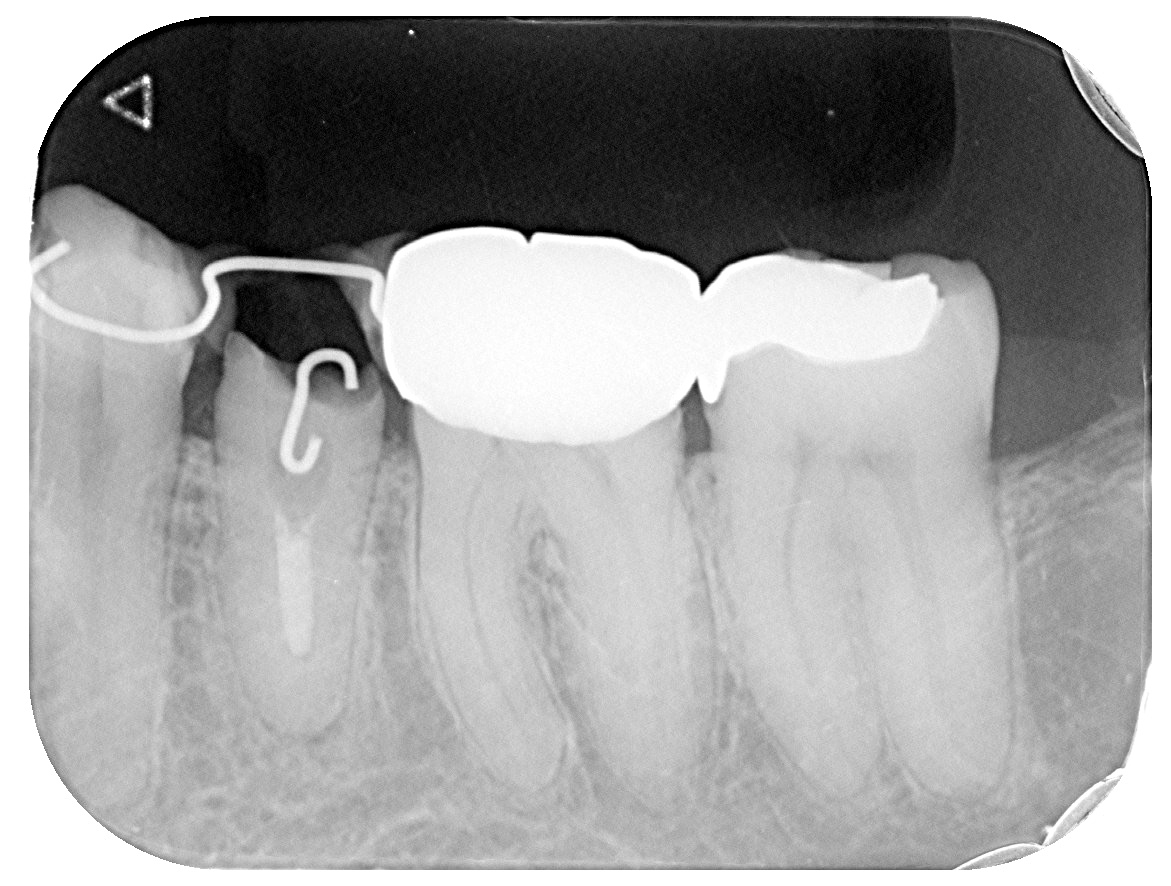

牽引レントゲン

牽引終了